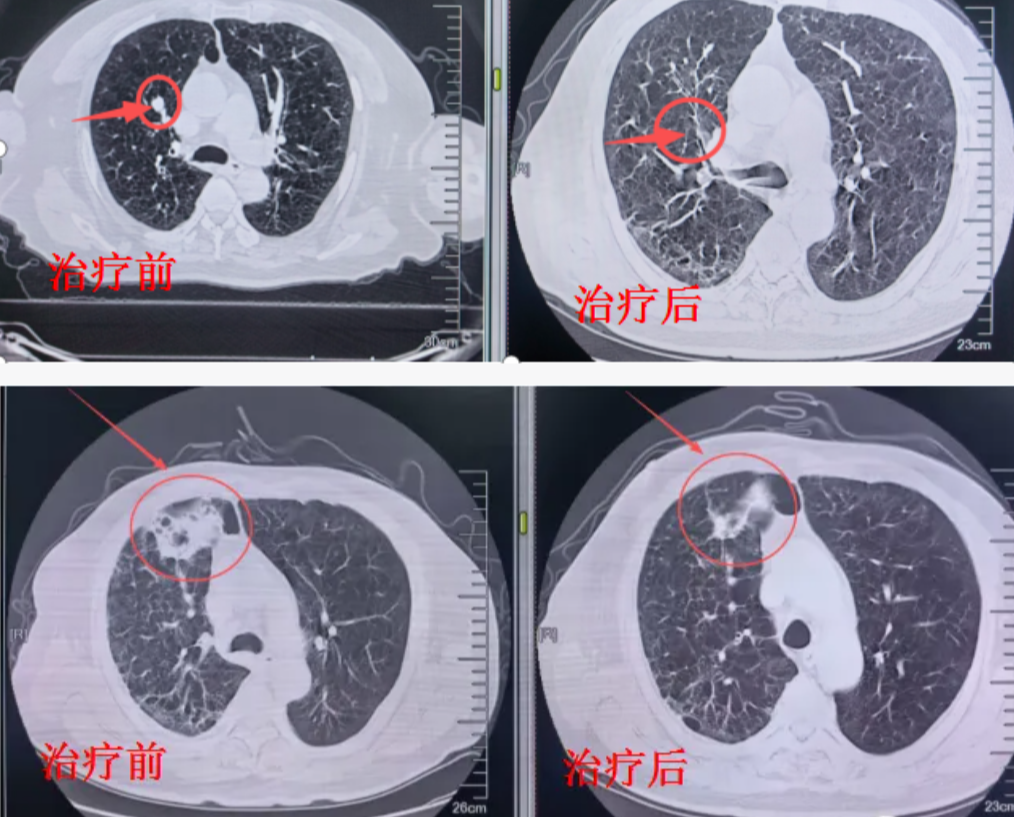

肺部肿瘤:早期肺癌患者的根治性选择,尤其适用于无法手术者,精准治疗肺转移瘤。

射波刀治疗案例